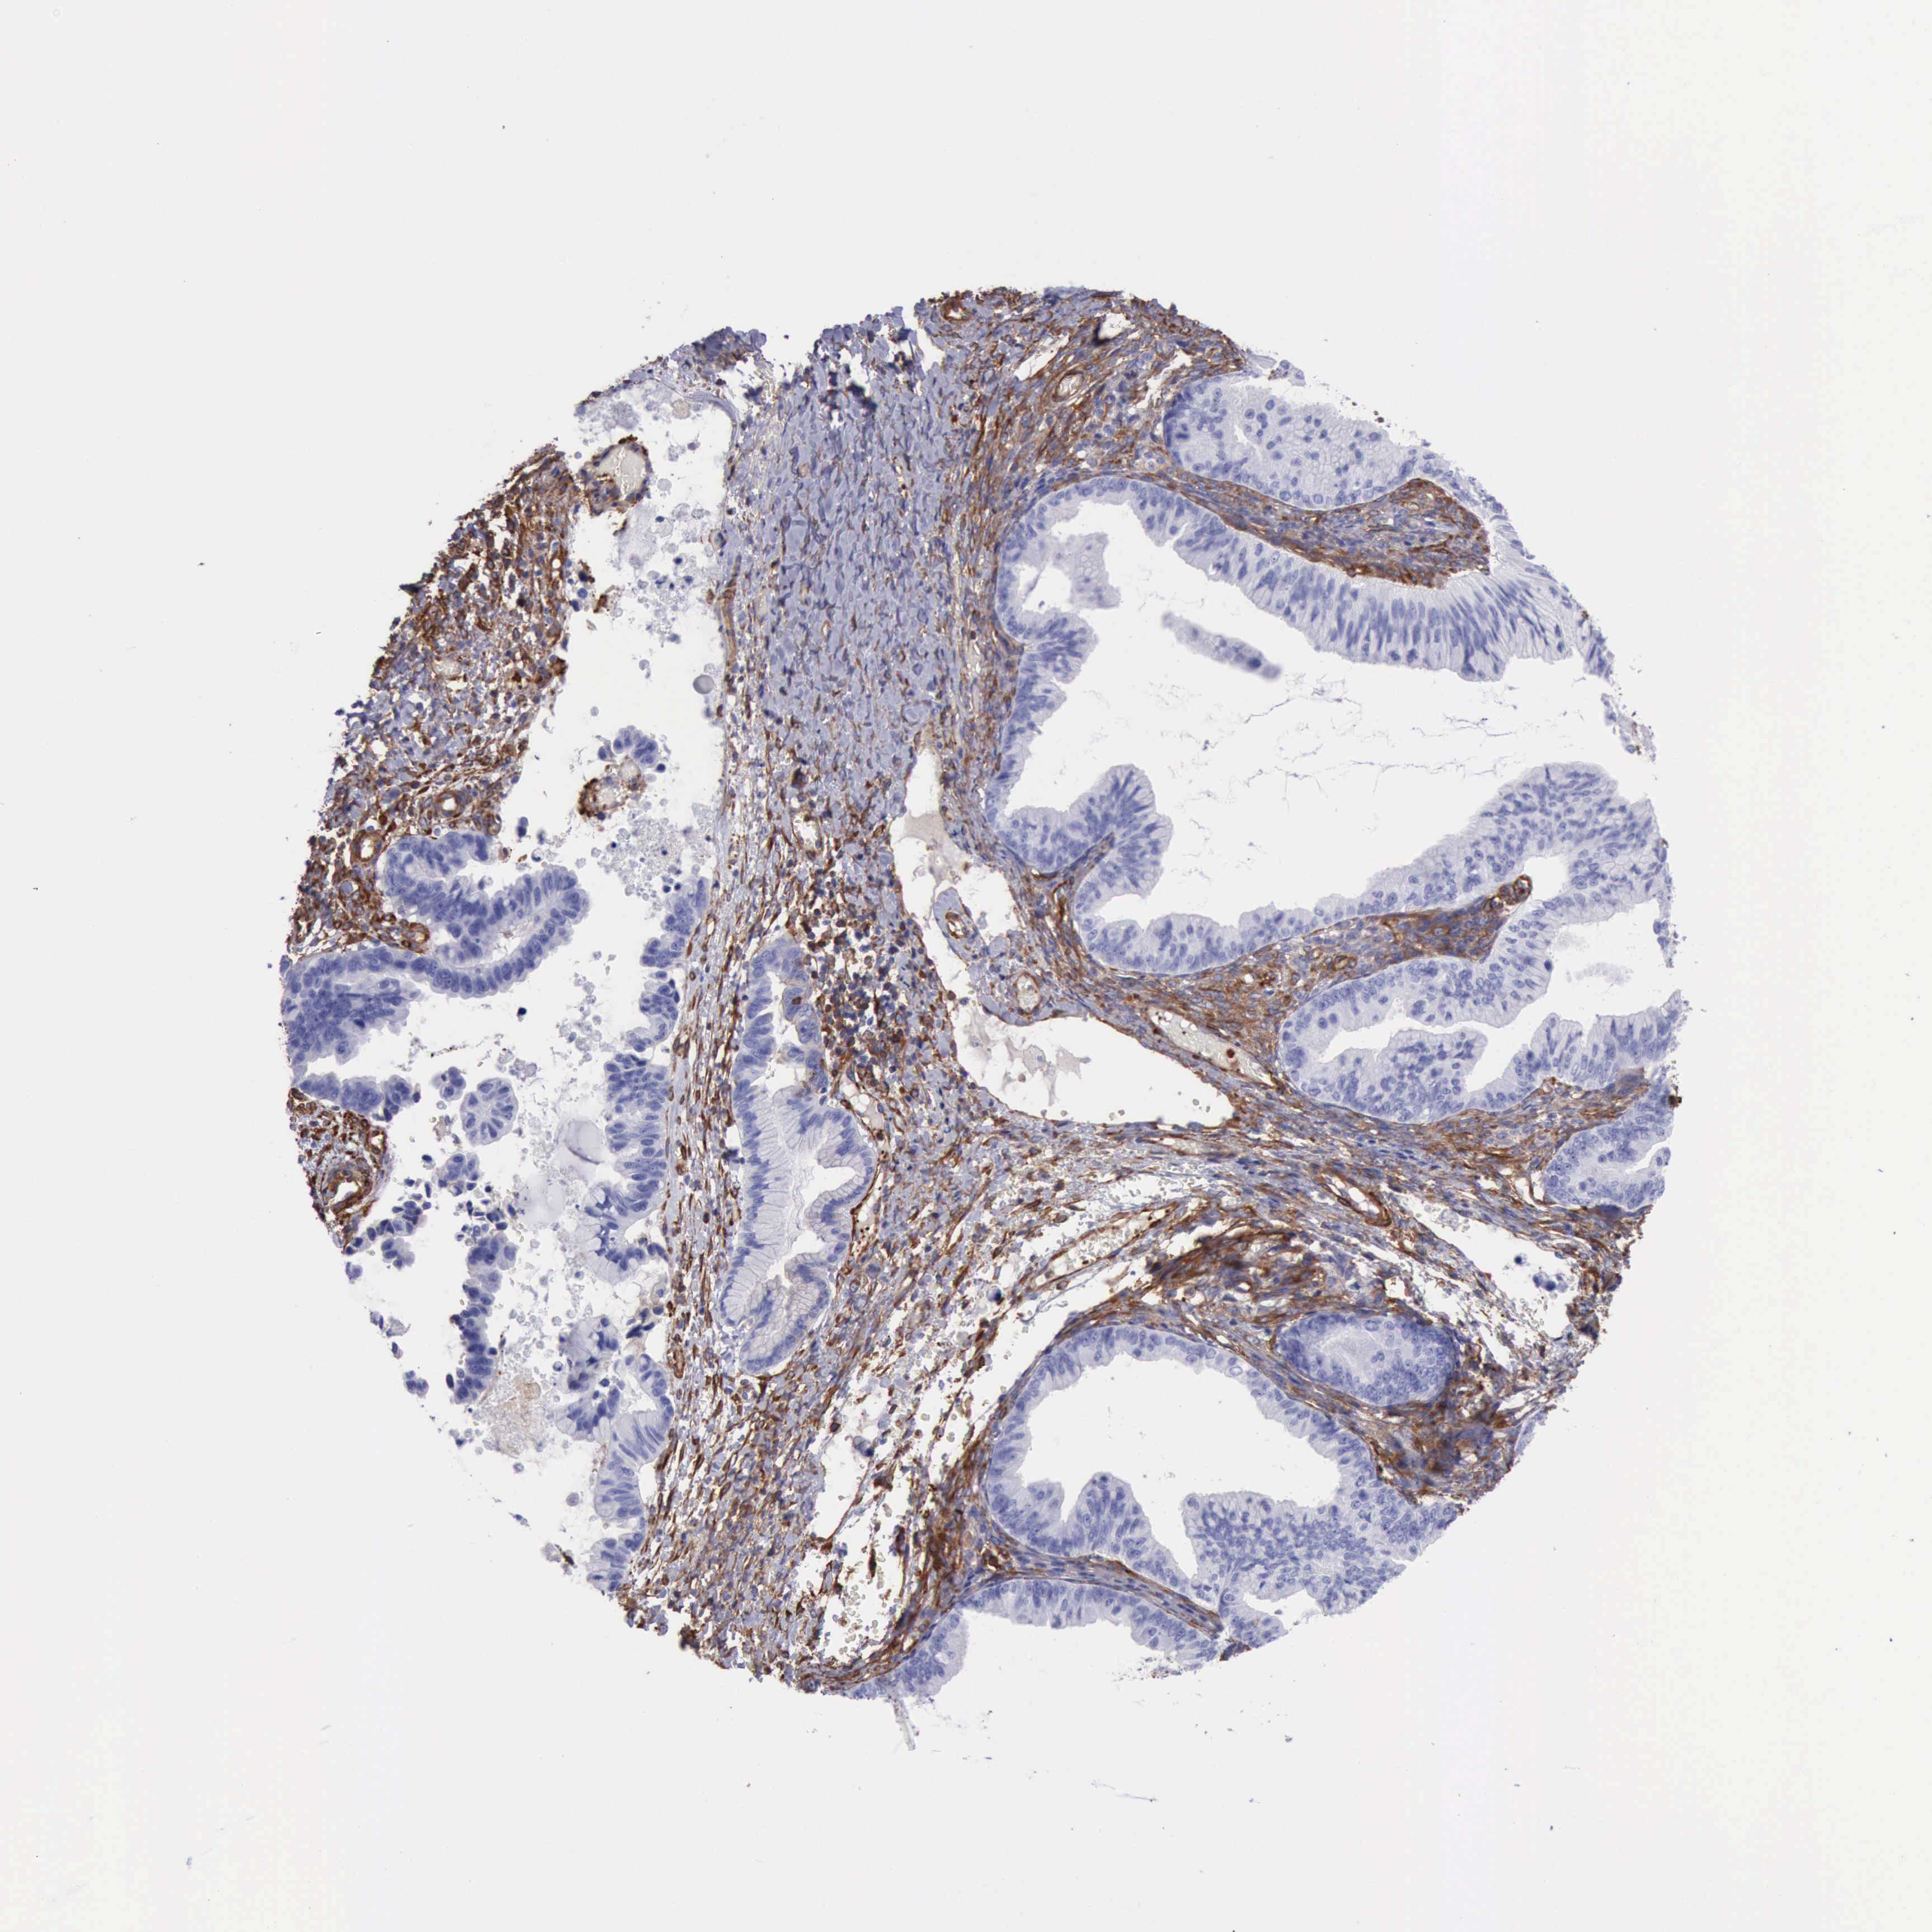

OVARIAN CANCER - Protein expressioni

A mouse-over function shows sample information and annotation data. Click on an image to view it in a full screen mode. Samples can be filtered based on level of antibody staining by selecting one or several of the following categories: high, medium, low and not detected. The assay and annotation is described here.

Note that samples used for immunohistochemistry by the Human Protein Atlas do not correspond to samples in the TCGA dataset.

Antibody stainingi

Antibody staining in the annotated cell types in the current human tissue is reported as not detected, low, medium, or high, based on conventional immunohistochemistry profiling in selected tissues. This score is based on the combination of the staining intensity and fraction of stained cells.

Each image is clickable and will lead to virtual microscopy that enables deeper exploration of all samples and also displays staining intensity scores, fraction scores and subcellular localization as well as patient and tissue information for each sample.

Antibody HPA001115

Antibody HPA002925

Antibody CAB000356

Staining

High

Medium

Low

Not detected

Cystadenocarcinoma, mucinous, NOS

Carcinoma, endometroid

Cystadenocarcinoma, serous, NOS